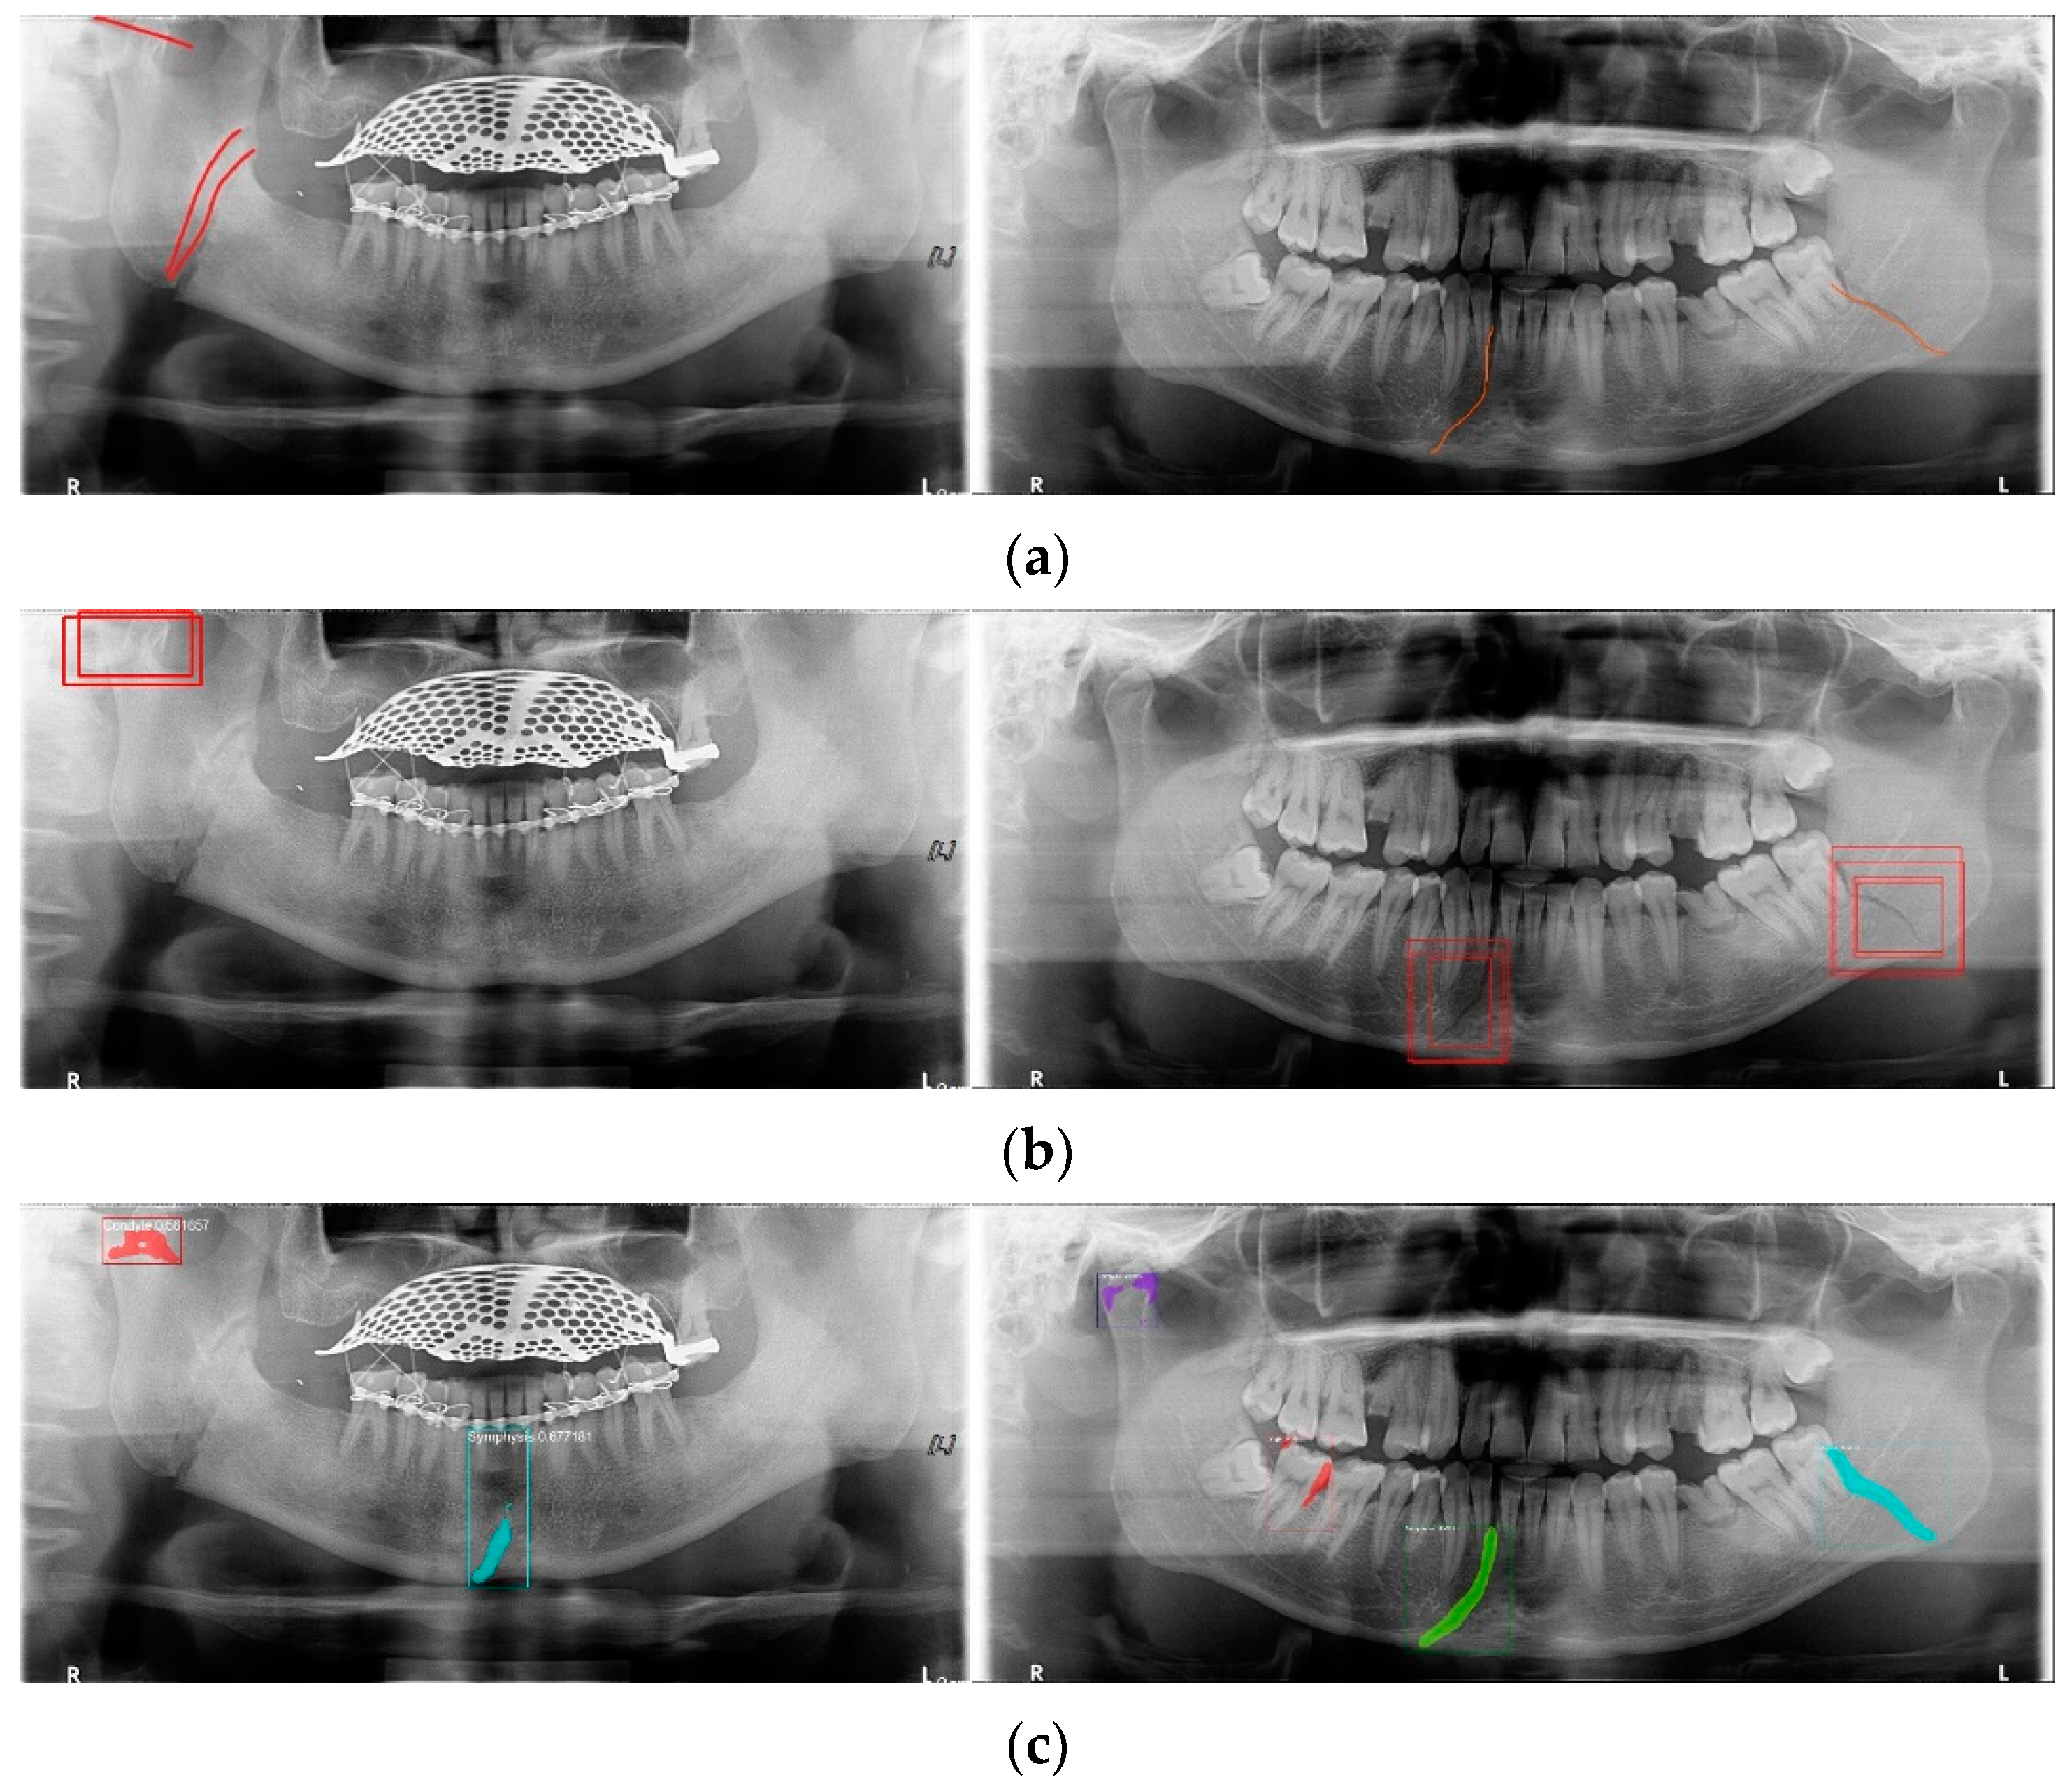

YOLO, Mask-R-CNN, and U-Net use different data-segmentation methods when constructing the training data. First, the mandibular fracture diagnosis module using Son et al.’s LAT YOLOv4 has a good diagnostic ability for fracture positions; however, it has a high undetected rate because it does not accurately distinguish fracture shapes and expresses fracture areas in the form of boxes. This module shows the diagnostic performance of precision of 97%, recall of 79%, and F1 score of 88%. In particular, fractures in the symphysis, body, angle, and ramus tend to be distributed in the middle of the mandible, and undiagnosed detection errors increase owing to irregular fracture shapes and overlapping location information. The advantage of location information is weakened; there is the possibility of a case where a fracture that is visible to the naked eye cannot be detected (Figure 3b). Therefore, additional applications such as Mask R-CNN, which is another object detection deep learning, and U-Net, which is used for medical image region segmentation, are needed to improve detection capabilities, especially recall scores representing undiagnosed performance in existing studies.

Figure 3.

The result of mandibular fracture detection: (a) diagnosis by oral and maxillofacial radiologist, (b) by LAT YOLOv4 module (with red boxes), (c) by Mask R-CNN (with colored polygons and boxes), and (d) by U-Net.

Unlike YOLO learning data consisting only of box coordinates and class information, Mask R-CNN requires the designation of a polygon-type learning region in the fracture region for the construction of a mandibular fracture learning dataset. However, in the case of shear fractures without gaps or dislocation fractures occurring in the condyle region, it was difficult to express the training data region using Mask R-CNN. Because these specific fracture regions cannot be drawn in closed polygon form, fracture regions are represented and trained in a box or simple form, such as YOLO learning data. In this case, for comparison with the results of the LAT YOLOv4 module [9], training was performed with the same class structure on the same training data, and the detection results in the same test data were 57% precision, 70% recall, and 63% F1 scores. The fracture shape of the condyle region is not properly expressed, which leads to an error in judgment owing to the fracture shape, and the error detection between teeth is also recognized as a fracture in the panoramic image, resulting in a lower precision score (Figure 3c).

For U-Net training, a training dataset labeled according to the shape of the fracture is constructed. This makes it easy to generate U-Net training datasets of fracture sites with complex spacing. However, shear fractures or displaced fractures are difficult to be labeled. Therefore, in the case of shear fractures, the parts which are visible even with solid and crack lines in the shear fractures were labeled as much as possible. But the displaced fractures were not labeled because it adversely affected the fracture detection accuracy during U-Net training. Additionally, when segmentation and labeling are performed differently from complex fracture shapes, it adversely affects the training process and reduces mandibular fracture detection performance. Figure 3d confirms that U-Net shows good segmentation performance for general fracture types but U-Net shows poor segmentation performance for dislocated fractures in the condyle region because U-Net was not trained in condyle region. Therefore, U-Net is advantageous for learning the rest of the fracture areas except for some of the severe shear and displaced fractures.